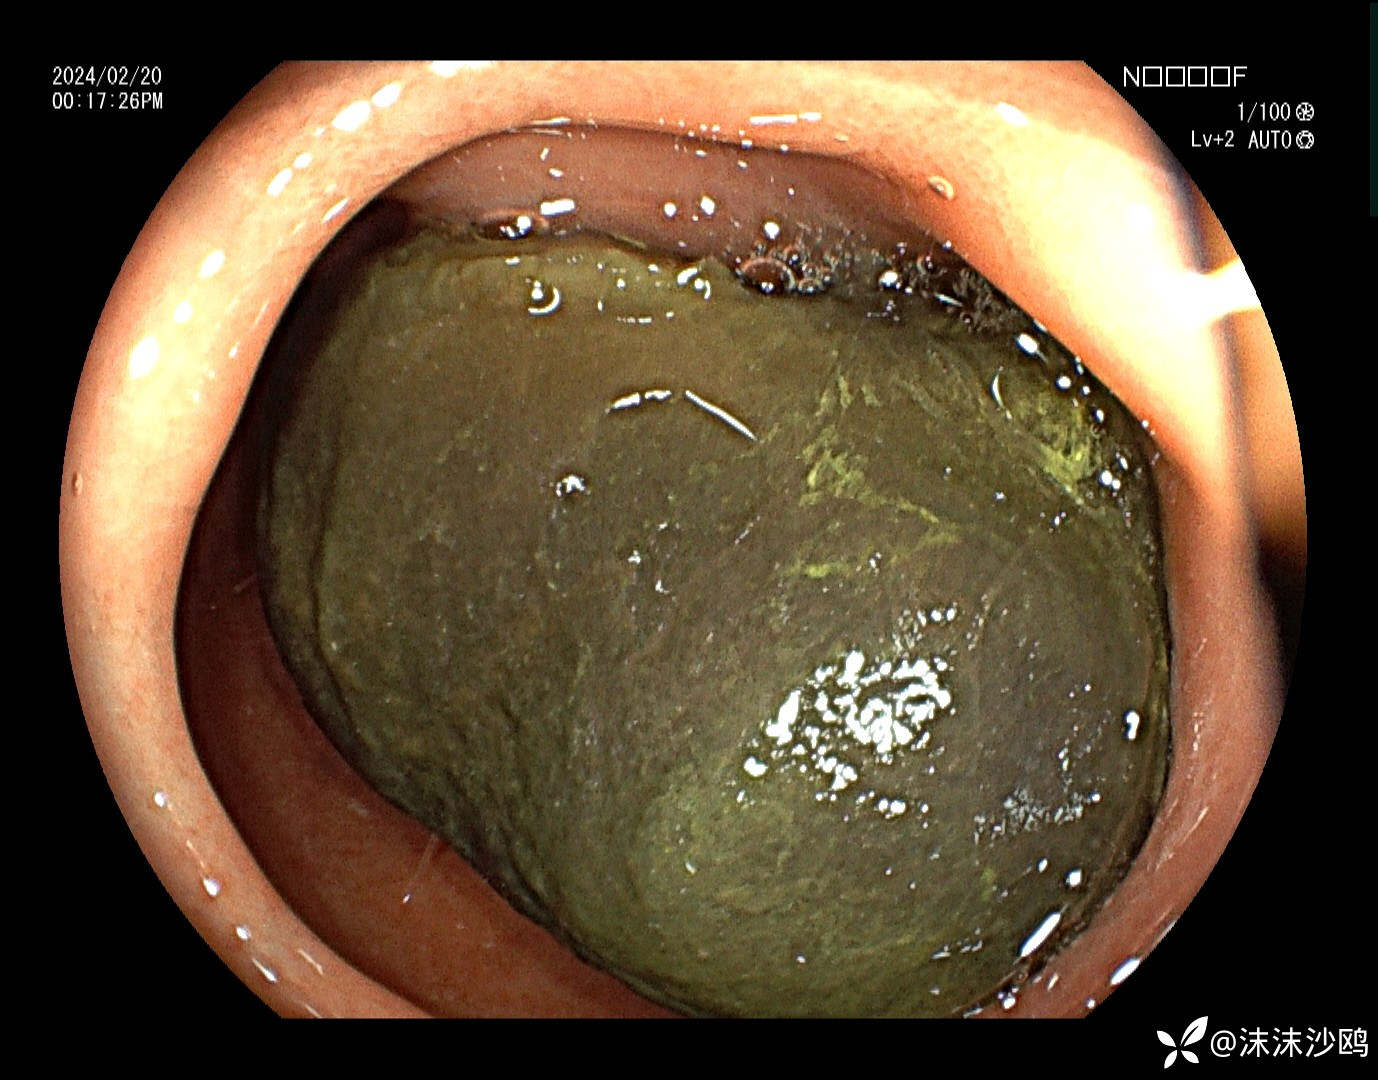

中年男子,腹痛就诊,行普通肠镜检查。胃腔内见大量胃液潴留,吸引了三四百毫升。进到幽门有了发现。

巨大异物嵌顿在球部,考虑胃石导致梗阻。询问病史,就是吃了几个车厘子,没有吃柿子或者山楂之类的。